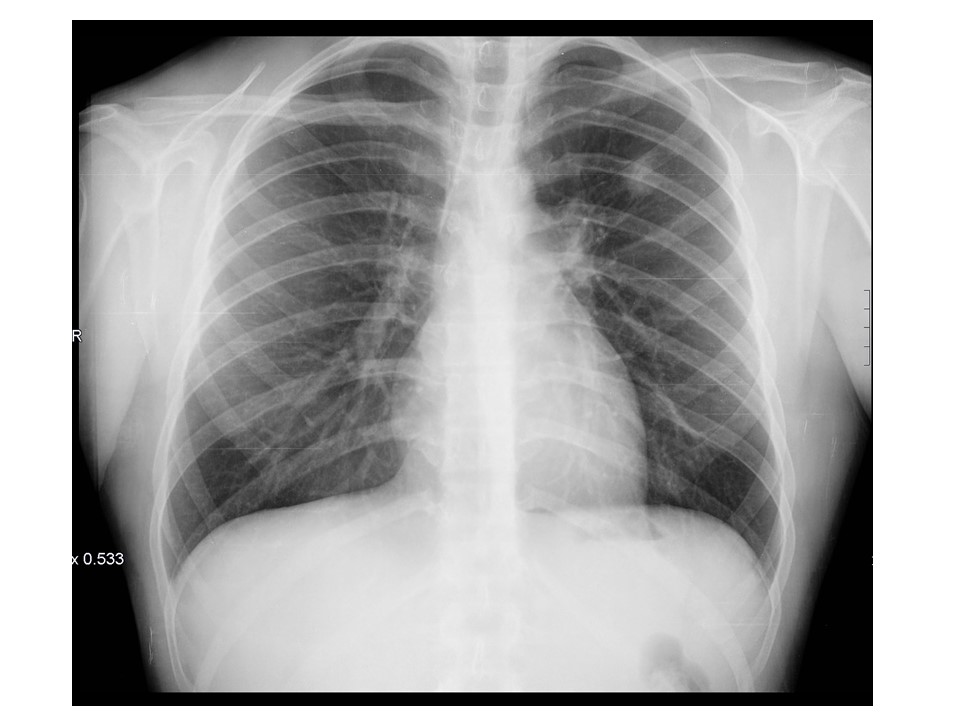

Razonamiento: Los rayos X, o radiografía, del tórax utilizan una dosis muy pequeña de radiación ionizante para producir imágenes del interior del tórax. Debido a su menor radiación, su rapidez y facilidad, la radiografía de tórax es la principal prueba de elección ante un dolor torácico, fiebre, tos persistente, lesiones o disnea.